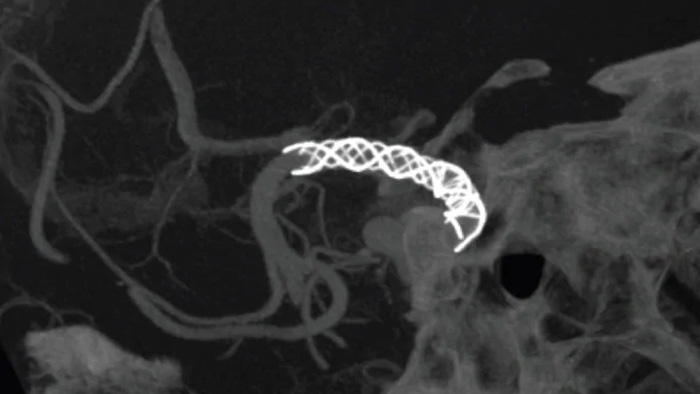

Vea claramente los perforadores cerebrales y los dispositivos desafiantes

SmartCT Vaso IA

Mejorar la vista de los stents endovasculares, los desviadores de flujo y otros dispositivos, así como la morfología de los vasos hasta el nivel del perforador con SmartCT Vaso. Esta técnica de adquisición se basa en una exploración por TC de haz cónico y una inyección de contraste intrarterial. Se utiliza cada vez más para el seguimiento de aneurismas tratados con stents desviadores de flujo para comprobar la posición del dispositivo.